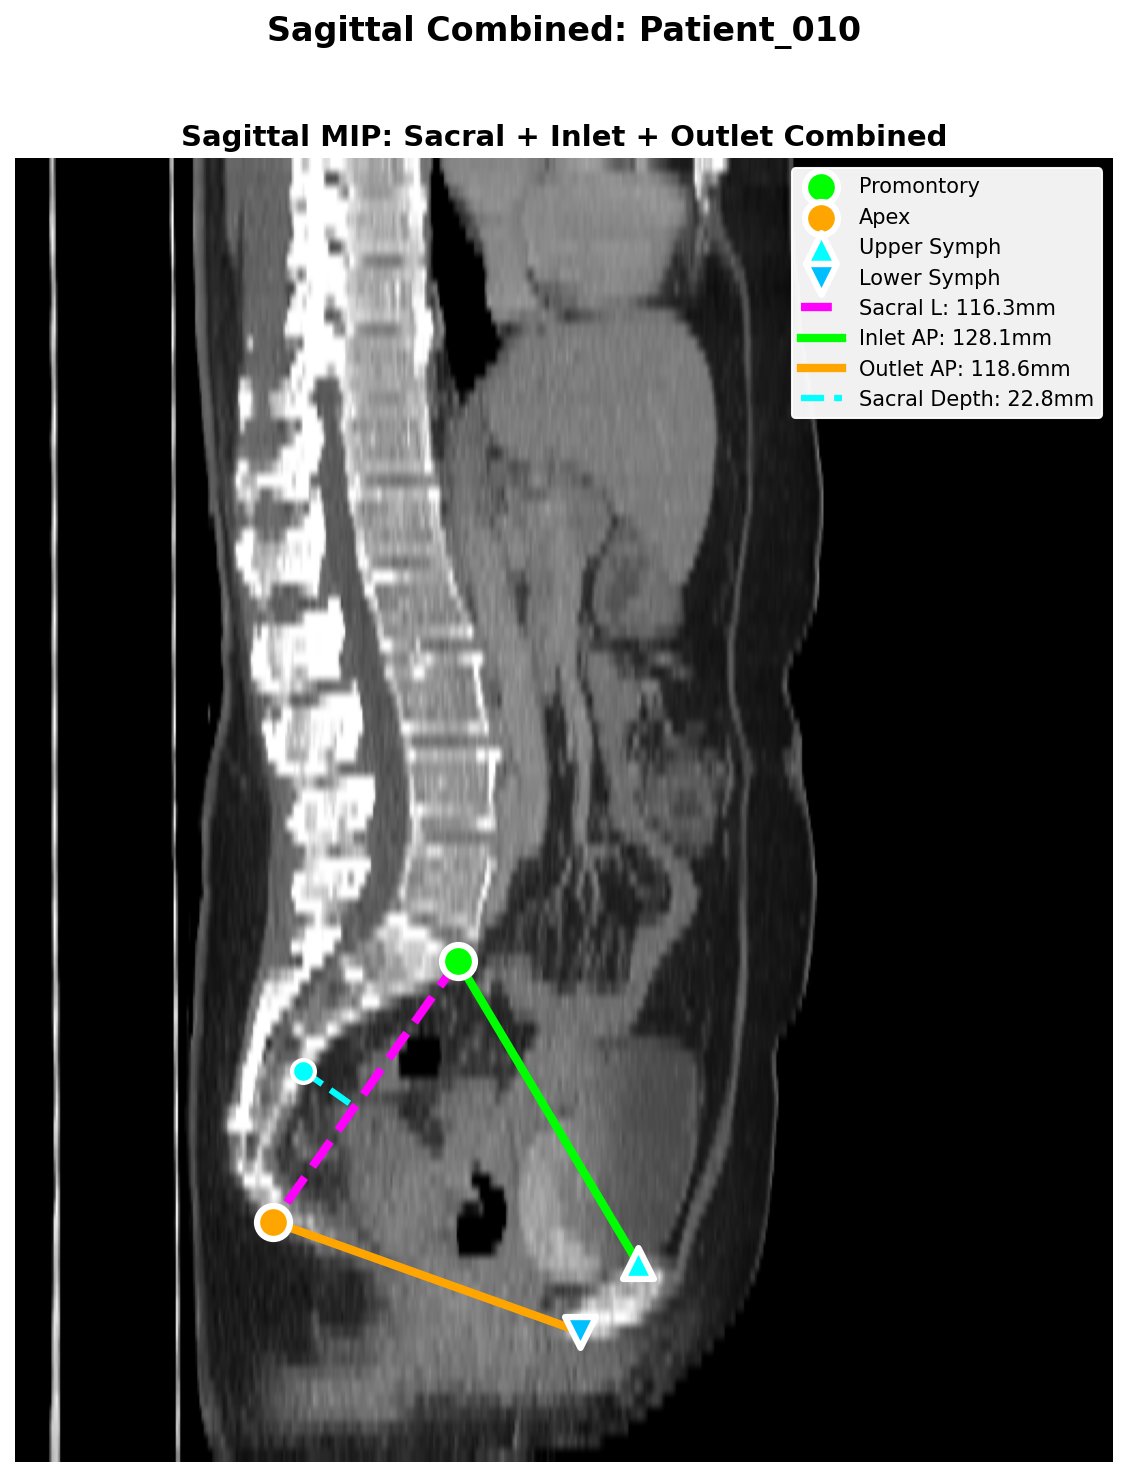

Sagittal QC figure showing automated landmark detection and pelvimetric measurements: sacral length (magenta), inlet AP (green), outlet AP (orange), and sacral depth (cyan).

| Inlet AP (mm) | Promontory → Upper Symphysis | | Outlet AP (mm) | Coccygeal Apex → Lower Symphysis | | Outlet Transverse (mm) | Intertuberous diameter | | Outlet Area (cm²) | Ellipse approx: π/4 × AP × Transverse | | Sacral Length (mm) | Promontory → Coccygeal Apex | | Sacral Depth (mm) | Max anterior concavity |